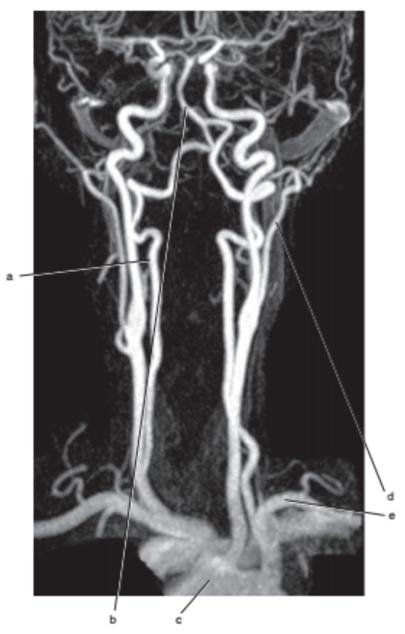

Vertebral artery

What is letter c ?

Aortic arch

What is letter b ?

External carotid artery

Subclavian artery

What is letter l ?

Common carotid

What is letter e ?

Common carotid artery

Carotid sinus/bifurcation